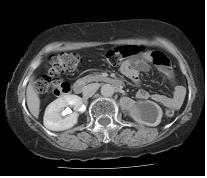

전산화단층촬영은 신우암과 신세포암의 감별에 도움이 되며, 신우와 요관암의 주위 장기로의 침범 여부나 림프선 혹은 원격 장기로의 전이 여부 등을 판단하는데 도움을 줍니다.

[ 전산화단층촬영 ]